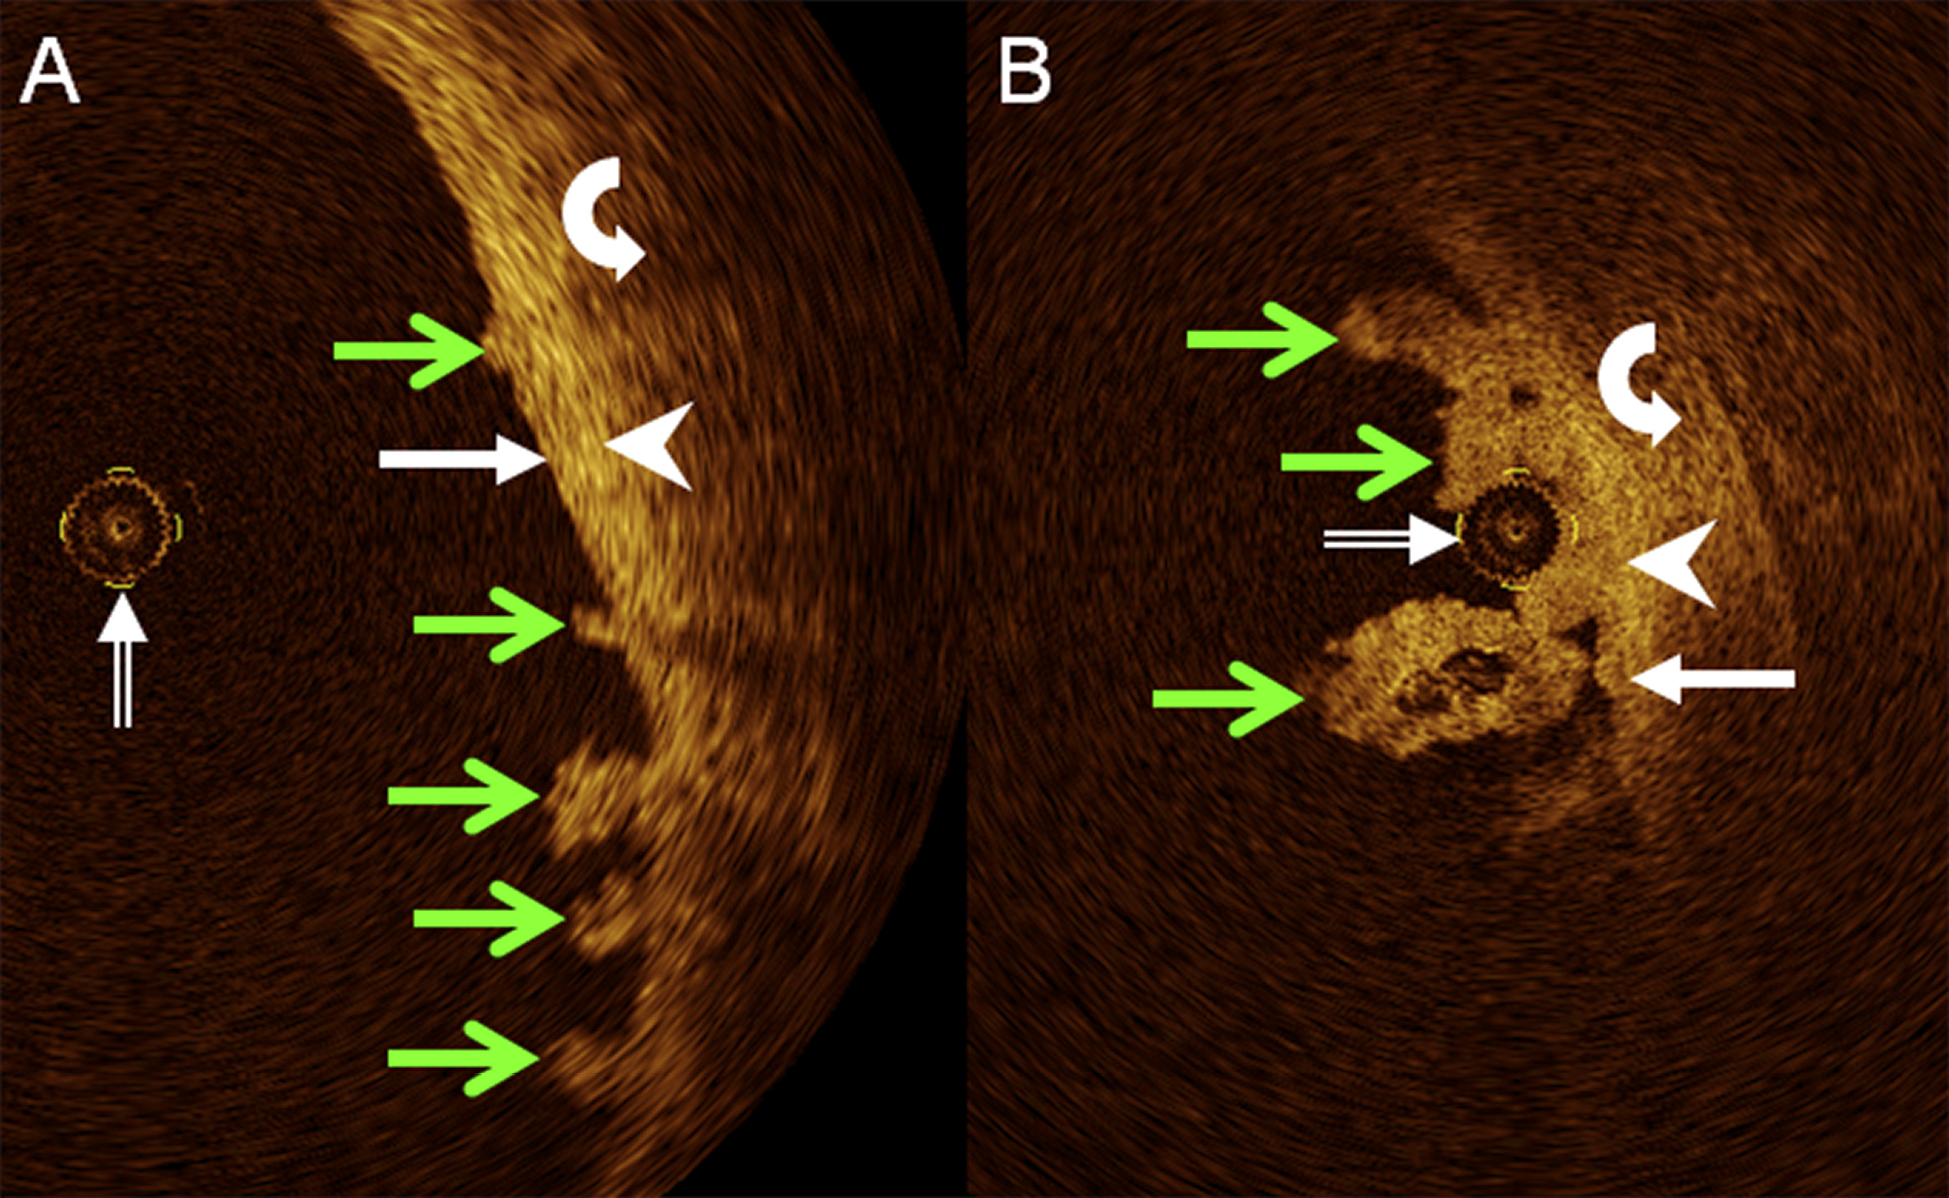

Figure 3. A. axial, cross-sectional OCT image of porcine upper ureter ex vivo, and B. corresponding digital light microscopy slide (H&E staining, low power, resolution appr. 4 μm) demonstrate urothelium (arrow), lamina propria (arrowhead), and muscle layer (curved arrow). The OCT probe shows in A (double-lined white arrow).

When comparing the 532 (68.2% of all samples) normal in-vivo human samples (Fig. 1 and Fig. 2) with 248 (31.8%) ex-vivo porcine OCT samples obtained (Fig. 3), there were no statistically significant differences in the distinction of any wall layers (porcine, 223, 90%, chi-square, 2.898, P = 0.089) and the distinction of lamina propria and muscle layer (porcine, 200, 81%, chi-square, 0.865, P = 0.352). However, porcine OCT samples significantly more often delineated urothelium and lamina propria (193, 78%, chi-square, 7.409, P = 0.006), different muscle layers (207, 84%, chi-square, 151.25, P < 0.001), and different cell layers within the urothelium (172, 69%, chi-square, 399.67, P < 0.001).

Distinction of three wall layers by means of OCT, as described previously [7-9,29] and corroborated here for normal porcine UUT ex vivo, was established, too, for normal human UUT in vivo. When compared with normal porcine UUT, OCT of human UUT demonstrated both any wall layers and distinction between lamina propria and muscle layer equally well, at no apparent loss of image quality. However, distinction of urothelium and lamina propria, and of cell layers within the urothelium were significantly better in normal porcine UUT ex vivo than in normal human UUT in vivo. Although it has previously been shown by histological analysis that the normal porcine upper urinary tract closely resembles the normal human upper urinary tract in its morphological structure, including the presence of four to five layers of urothelium, one distinctive difference lies in the inclusion of mucinous cells within the urothelium in porcine, but not in human UUT [30]. We cannot provide immediate evidence of an effect of the presence of mucinous cells on the ability of OCT to distinguish between the urothelium and lamina propria or between different urothelial cell layers. However, indirect evidence may derive from the fact that the lamina propria and muscle layer delineated equally well in the porcine model and in human UUT, such that anatomical differences in urothelial structure appear to be a more likely reason than technical differences between porcine and human OCT studies. It may be hypothesized that one factor contributing to the superior delineation by OCT of different UUT muscle layers in the porcine model was its ex-vivo state, without ureteral peristalsis, when compared to human UUT in vivo.